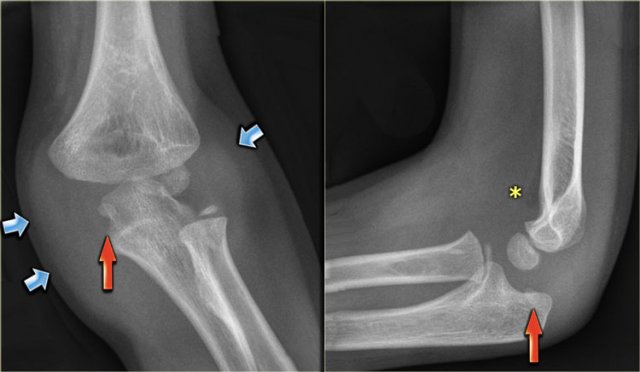

1. There is enormous soft tissue swelling, which indicates that the elbow has been dislocated (blue arrows). So the next question is where is the medial epicondyle?

2. The medial epicondyle is seen entrapped within the joint (red arrows).

3. Notice that there is only minor joint effusion (asterix). The medial epicondyle is an extra-articular structure and avulsion will not produce joint effusion. The small amount of joint effusion is probably the result of the prior dislocation.